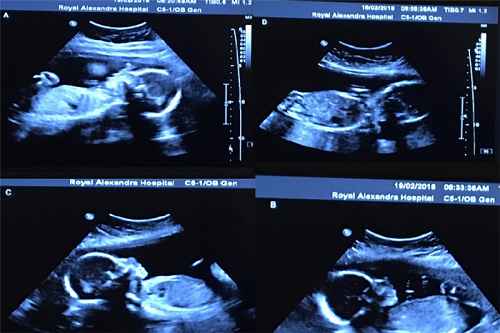

But soon after visiting the doctor, Bethani discovered that her pregnancy was not typical. And when it came time for the ultrasound, she saw that she was carrying four embryos. And with that knowledge, her love for her unborn children grew even stronger.

Her expected C-section date finally arrived. The date was May 6, 2016. And it turned out to be one of only 15 million days.

The doctors and nurses present in the room were amazed at what they saw when all four babies were born. There were identical quadruplets. Because of how unusual it is, you might as well go play Powerball.